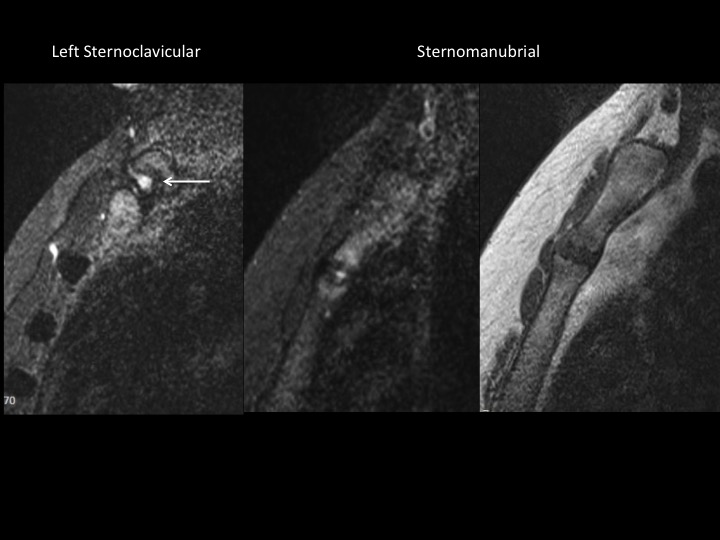

The referrer ordered MRI of each clavicle, but the left side included the manubrium and upper sternum as well at the medial right clavicle. Symptoms are only near the left sternoclavicular joint. There are bilateral bright foci in the articular cartilage of the medial clavicle (white arrows), with subtle subchondral erosion but no BME on the left. There is left sided subchondral edema at the costomanubrial junction (yellow arrows). Obvious erosion with edema at the manubriosternal articulation The referrer did not notice any rash, though it sounds like he didnt think to look. Im thinking SAPHO and seronegative spondyloarthropathies; agree or not? The orthopedist says he will refer him to rheumatologist and will get me follow up when available. Reference article.

manubrium ( RID2476 )